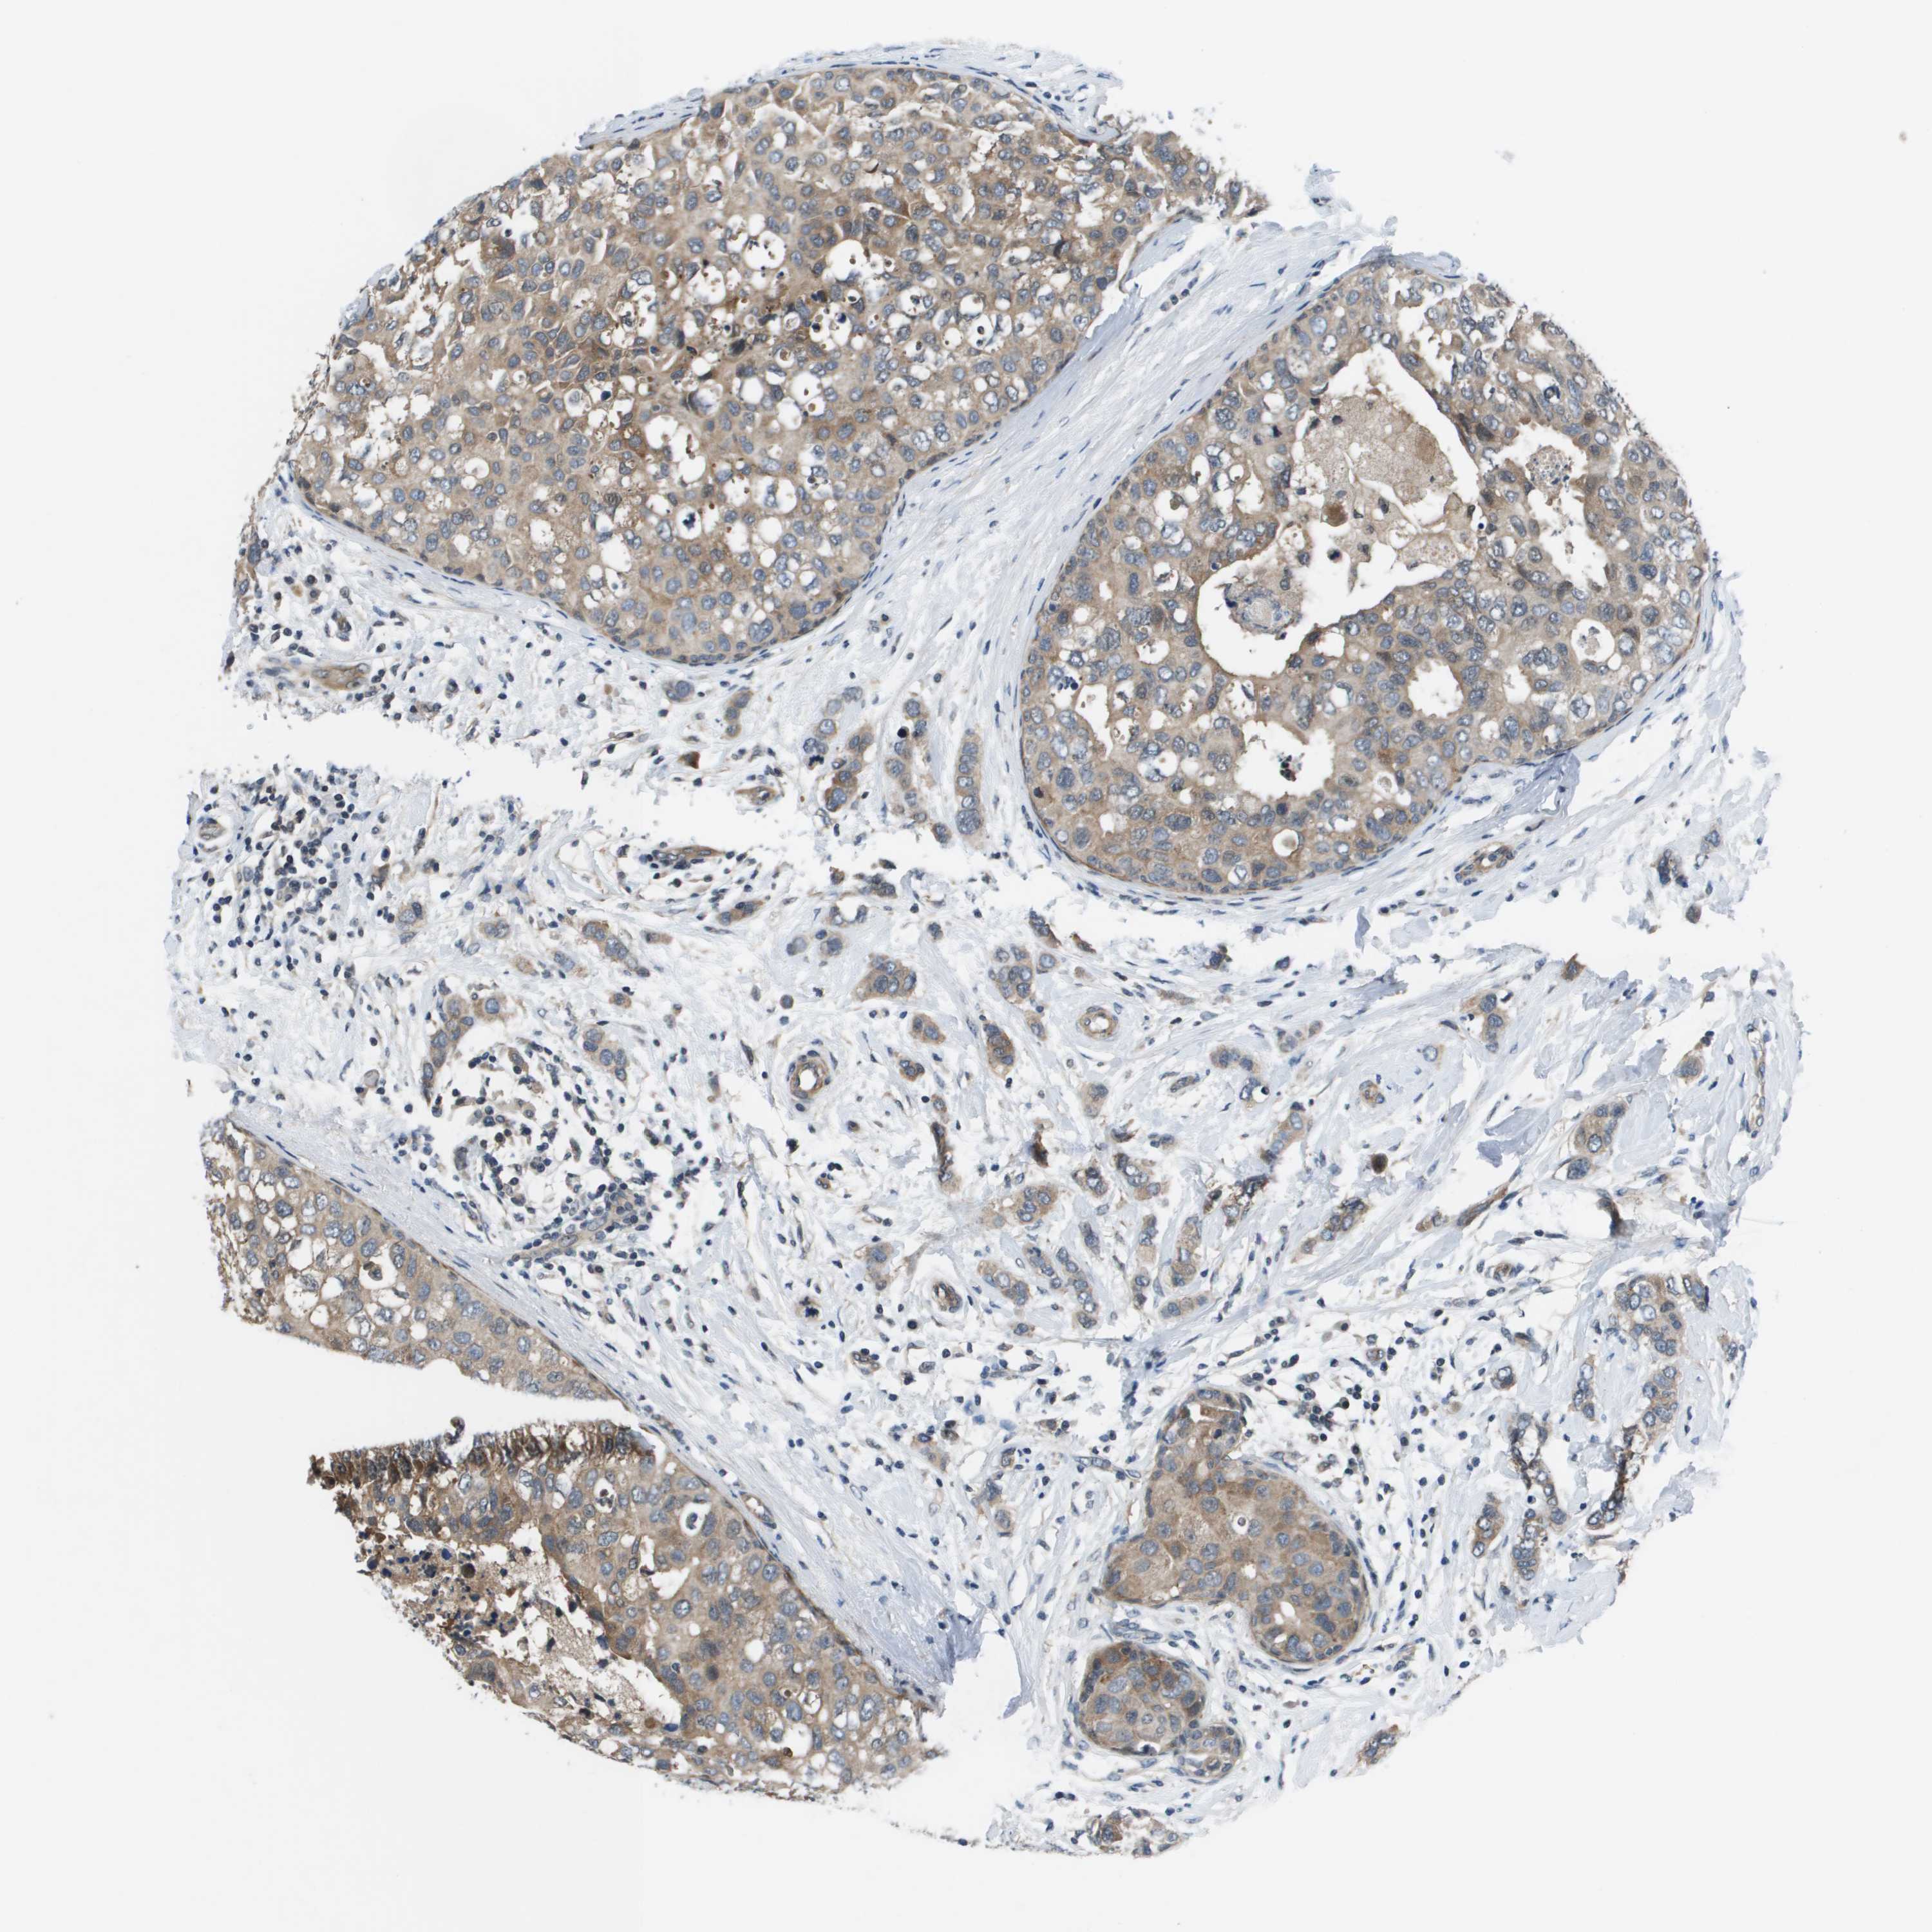

CANCER BREAST CANCER Show tissue menu

BRCA TCGA BRCA VALIDATION PROTEIN EXPRESSION